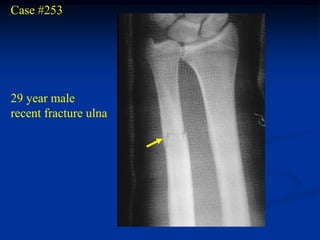

Case #253

29 year male

recent fracture ulna

18 months later

with desmoid tumor

at fracture site

Sagittal T-2 MRI 18 months later with desmoid tumor

Axial T-2 MRI at 18 months